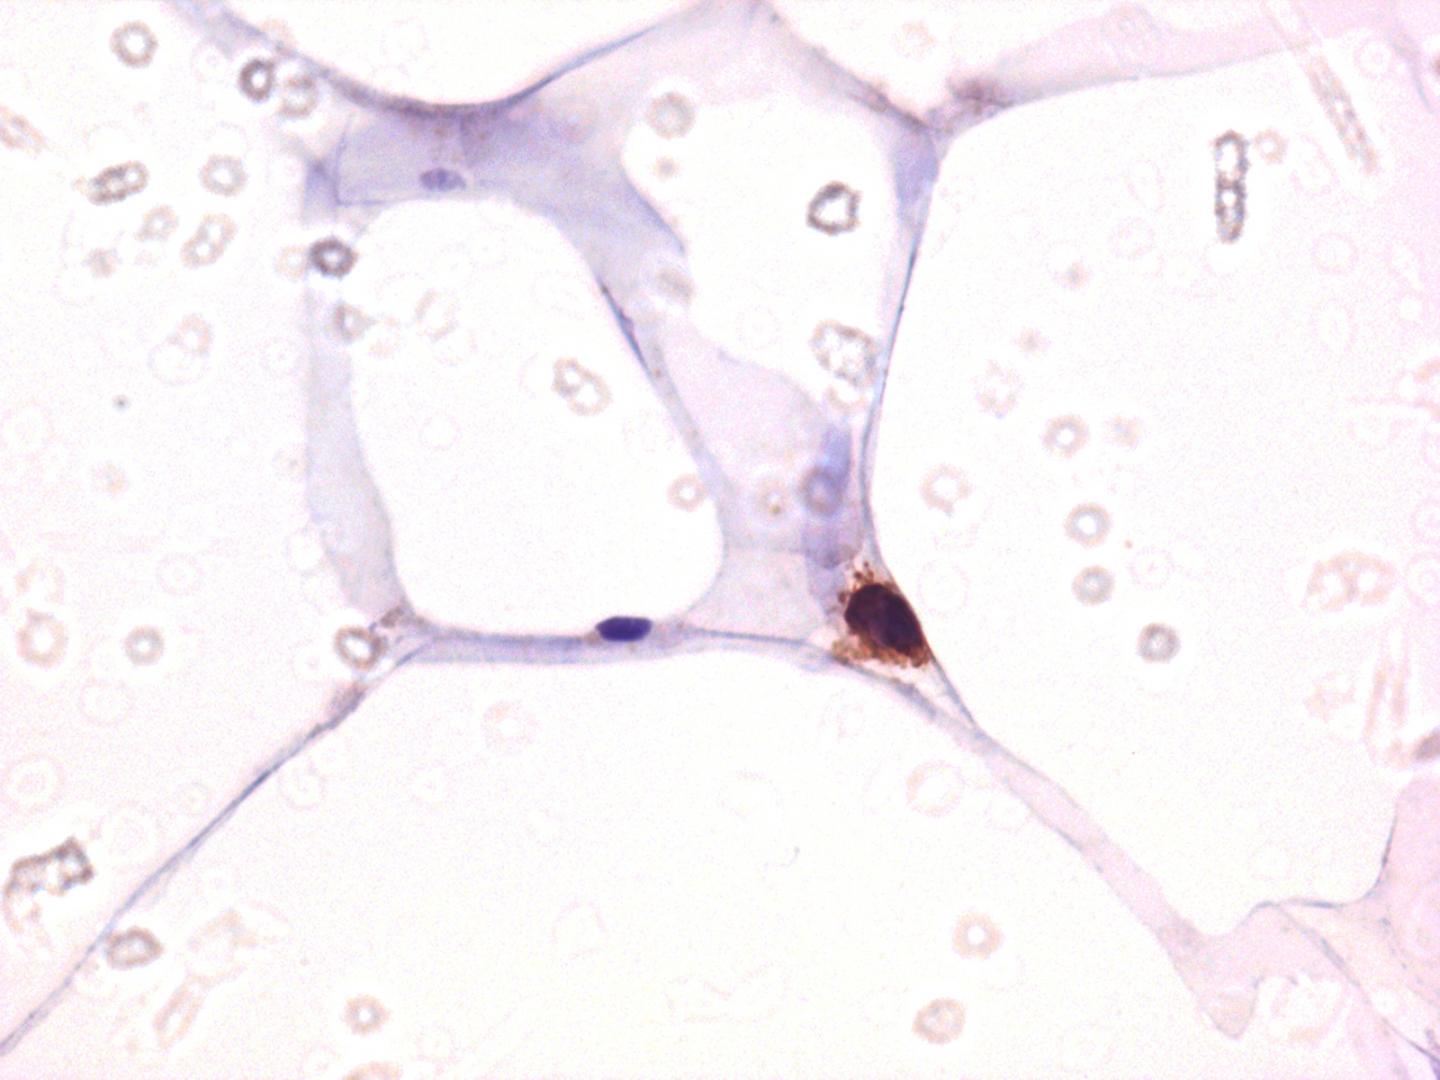

CD4 staining among adipose tissue demonstrating that the main target of HIV, i.e. CD4 T cells, is indeed detectable in adipose tissue.

CC-BY Damouche et al.